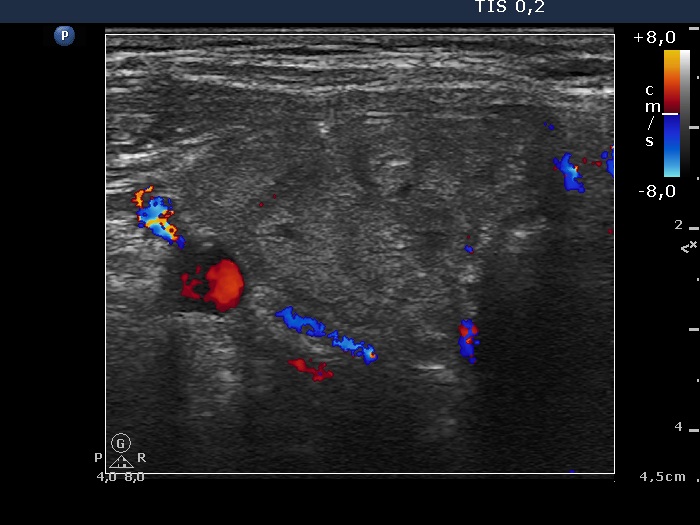

Ultrasonography. The thyroid was minimally hypoechogenic and had multiple discrete lesions which were mostly echonormal. The thyroid had a pseudonodular pattern. There were several hypoechogenic discrete areas.